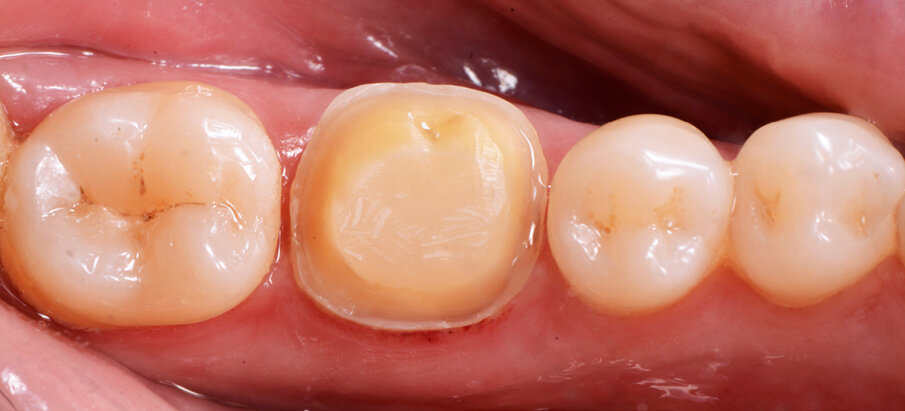

Figs. 12a & b: Lateral and occlusal views of the completed restoration.

A 45-year-old male patient presented to the practice with a restoration on tooth #46. The tooth had been endodontically treated and temporised with a filling (Fig. 1). The temporary was removed, the tooth built up with Tetric N-Ceram Bulk Fill (Ivoclar Vivadent) and then prepared for the crown restoration (Fig. 2). An impression was taken with a one- step, two-phase impression technique using a putty and light-body silicone. After scanning the model, the crown was designed in the software suite (inLab, Dentsply Sirona) and milled from an IPS e.max CAD lithium disilicate block (Ivoclar Vivadent; Figs.3a & b). After the crystallisation fir- ing, the crown was stained and glazed (Fig. 4). The next step was to etch and silanate the ceramic crown with the new glass-ceramic primer Monobond Etch & Prime (Ivoclar Vivadent). This primer combines a ceramic etching and silanating component in a single material and therefore eliminates the need for the ceramic to undergo hydrofluoric acid etching (Fig. 5). After the etching and silanating step, the crown was rinsed with water and dried. The isolated enamel was then etched (Fig. 6). The adhesive (Tetric N-Bond Universal) was applied and dispersed with a strong stream of air. The dual-curing version of the Variolink Esthetic luting composite was used for seating owing to the thickness of the crown and the low translucency of the ceramic material (Fig. 7). The luting composite was applied into the crown. The restoration was then seated (Fig. 8) and light-cured from each side for two seconds. Excess composite was easy to remove owing to the Ivocerin photoinitiator (Ivoclar Vivadent), which provides a fast and thorough cure with a minimum amount of energy (Fig. 9). For final polymerisation, the restoration was light-cured from each quarter for 20 seconds (Fig. 10). Figures 11 and 12a & b show the oral situation after placement of the crown. Although the cement line was located above the gingival margin, it was not visible owing to the favourable tone and opacity of the luting composite. Figures 13a & b show radiographic control images of the restoration: the radiopaque build-up material and cement can easily be distinguished from the tooth structure. This aspect is particularly important in situations where excess cement cannot be seen with the naked eye.